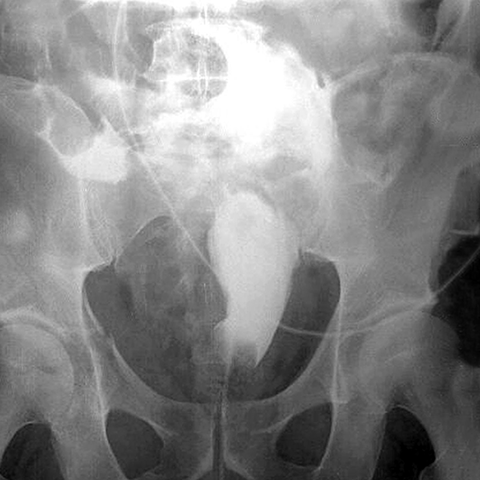

Bladder upture, cystogram [1 of 2]